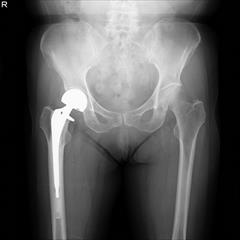

スポーツや事故による骨折や靱帯断裂などの外傷、腰部脊柱管狭窄症や腰椎椎間板ヘルニア、頚椎性脊髄症などの脊椎疾患、変形性膝関節症や変形性股関節症などの慢性疾患、骨粗鬆症などを当科では診療しています。また当科で扱わない特殊な分野の疾患に対しては適切な専門施設にご紹介させていただいております。

骨折や靱帯断裂などの外傷に対しては、単純レントゲン写真に加えて、必要に応じCT検査やMRI検査を追加して、的確な治療法を提供します。特に関節周辺の骨折は積極的に手術療法を行い、機能障害が残らないように心がけています。 脊椎変性疾患は外来で徹底した保存療法を行い、痛みや歩行障害が顕著なものには、適応を選んで除圧術や固定術を行っています。 変形性膝関節症や変形性股関節症などの慢性疾患に対しては、患者様の状態や重症度にあわせて、保存治療(手術をしない治療)から手術治療までを提供致します。脊椎や関節疾患に関して内視鏡などの医療機器(最先端のフルハイビジョンシステム)を駆使した手術も行っています。 最近では、高齢患者様が急増していますが、経験豊富な療法士が受傷翌日、手術翌日からリハビリを行い、元の生活レベルまで回復できるよう努めています。 なお、当院には回復期リハビリ病棟がありますので、疾患によっては術後のリハビリテーションに十分時間をかけて治療を行っています。

変形性膝・股関節症、リウマチ性関節炎、特発性骨壊死症、膝半月板損傷や十字靱帯・側副靱帯損傷を含む膝スポーツ外傷の診療を行っています。